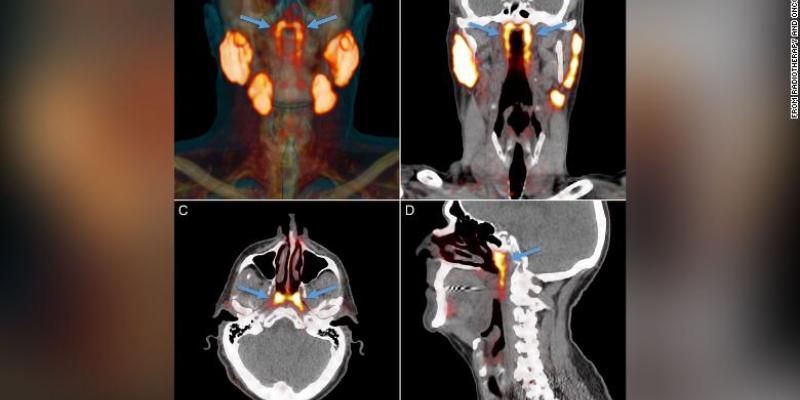

Las glándulas no se pueden ver con métodos convencionales de imágenes médicas como ultrasonido, tomografías computarizadas o imágenes de resonancia magnética. El nuevo órgano solo se identificó cuando los médicos utilizaban un tipo de exploración nuevo y avanzado llamado PSMA PET/CT que se ha utilizado para detectar la propagación del cáncer de próstata.

PSMA PET es la abreviatura de la obtención de imágenes de antígeno de membrana específico de la próstata mediante tomografía por emisión de positrones. "Las personas tienen tres conjuntos de glándulas salivales grandes, pero no allí". Así dijo el autor del estudio Wouter Vogel, un oncólogo radioterapeuta del Instituto del Cáncer de los Países Bajos.